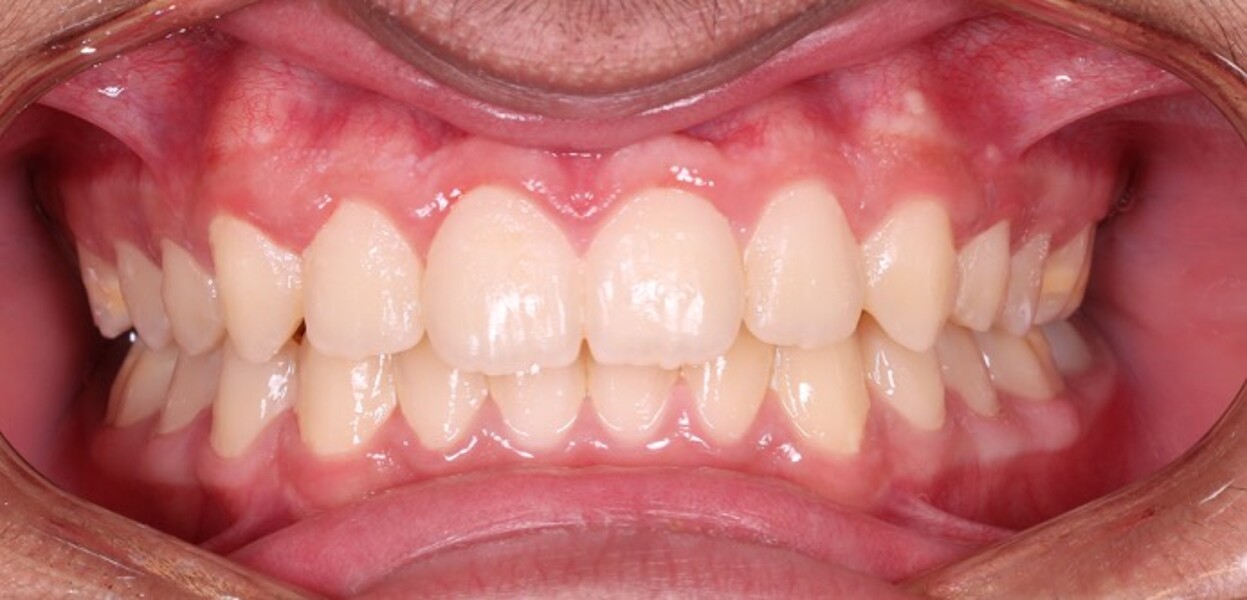

Figs. 8a–e: Intra-oral photographs after the second phase of treatment.

Fig. 8b

Fig. 8c

Fig. 8d

Fig. 8e

The final records demonstrated (Figs. 7–9; Table 2):

stable bilateral Class I molar and canine relationships;

normalised overjet and overbite;

well-aligned dental midlines coinciding with the facial midline;

fully developed, symmetric and parabolic dental arches; and

absence of root resorption and satisfactory root parallelism.

Radiographic evaluation showed symmetrical mandibular structures and normally seated condyles, and no pathology was detected. The findings showed correction of the skeletal Class II relationship primarily through improvement in mandibular position, as well as showed normalisation of overjet and overbite and establishment of a more balanced skeletal and dental relationship.